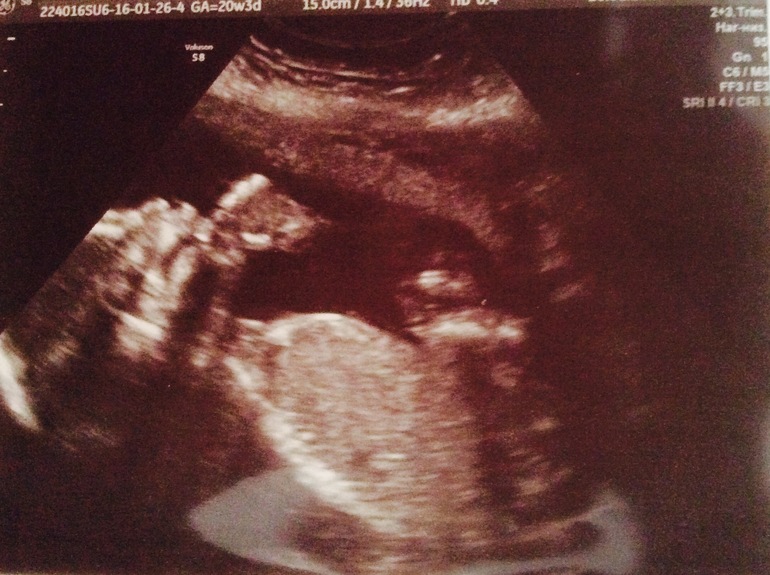

Всё о нашей беременностиИ снова здравствуйте мои дорогие девчули!!! Вот и прошёл мой 2ой скрининг😊 всё замечательно, малыш поначалу повернулся своей попкой и ни в какую не давался нам посмотреть его, мой хулигашка! Но всё же сдался нам))) лежал, открывал рот, показывал язык и сосал палец))) срок по УЗИ на 2 дня побольше акушерского, почти таки сровнялся! На сегодняшний момент нам 20 недель и 5 дней😊

А вот несколько фоток моего хулигашки🤗